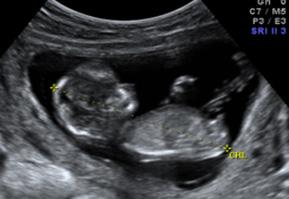

Certeza: La ecografía transvaginal es la prueba confirmatoria de embarazo. A las 4.5 semanas, se observa saco gestacional; a las 5 semanas, se encuentra embrión, y a las 6 semanas es posible auscultar los latidos cardiacos fetales con el doppler . También se considera la percepción de movimientos fetales por parte del médico.

Figura 11. Ecografía de I trimestre Examen de certeza para confirmar un embarazo eutópico y viable